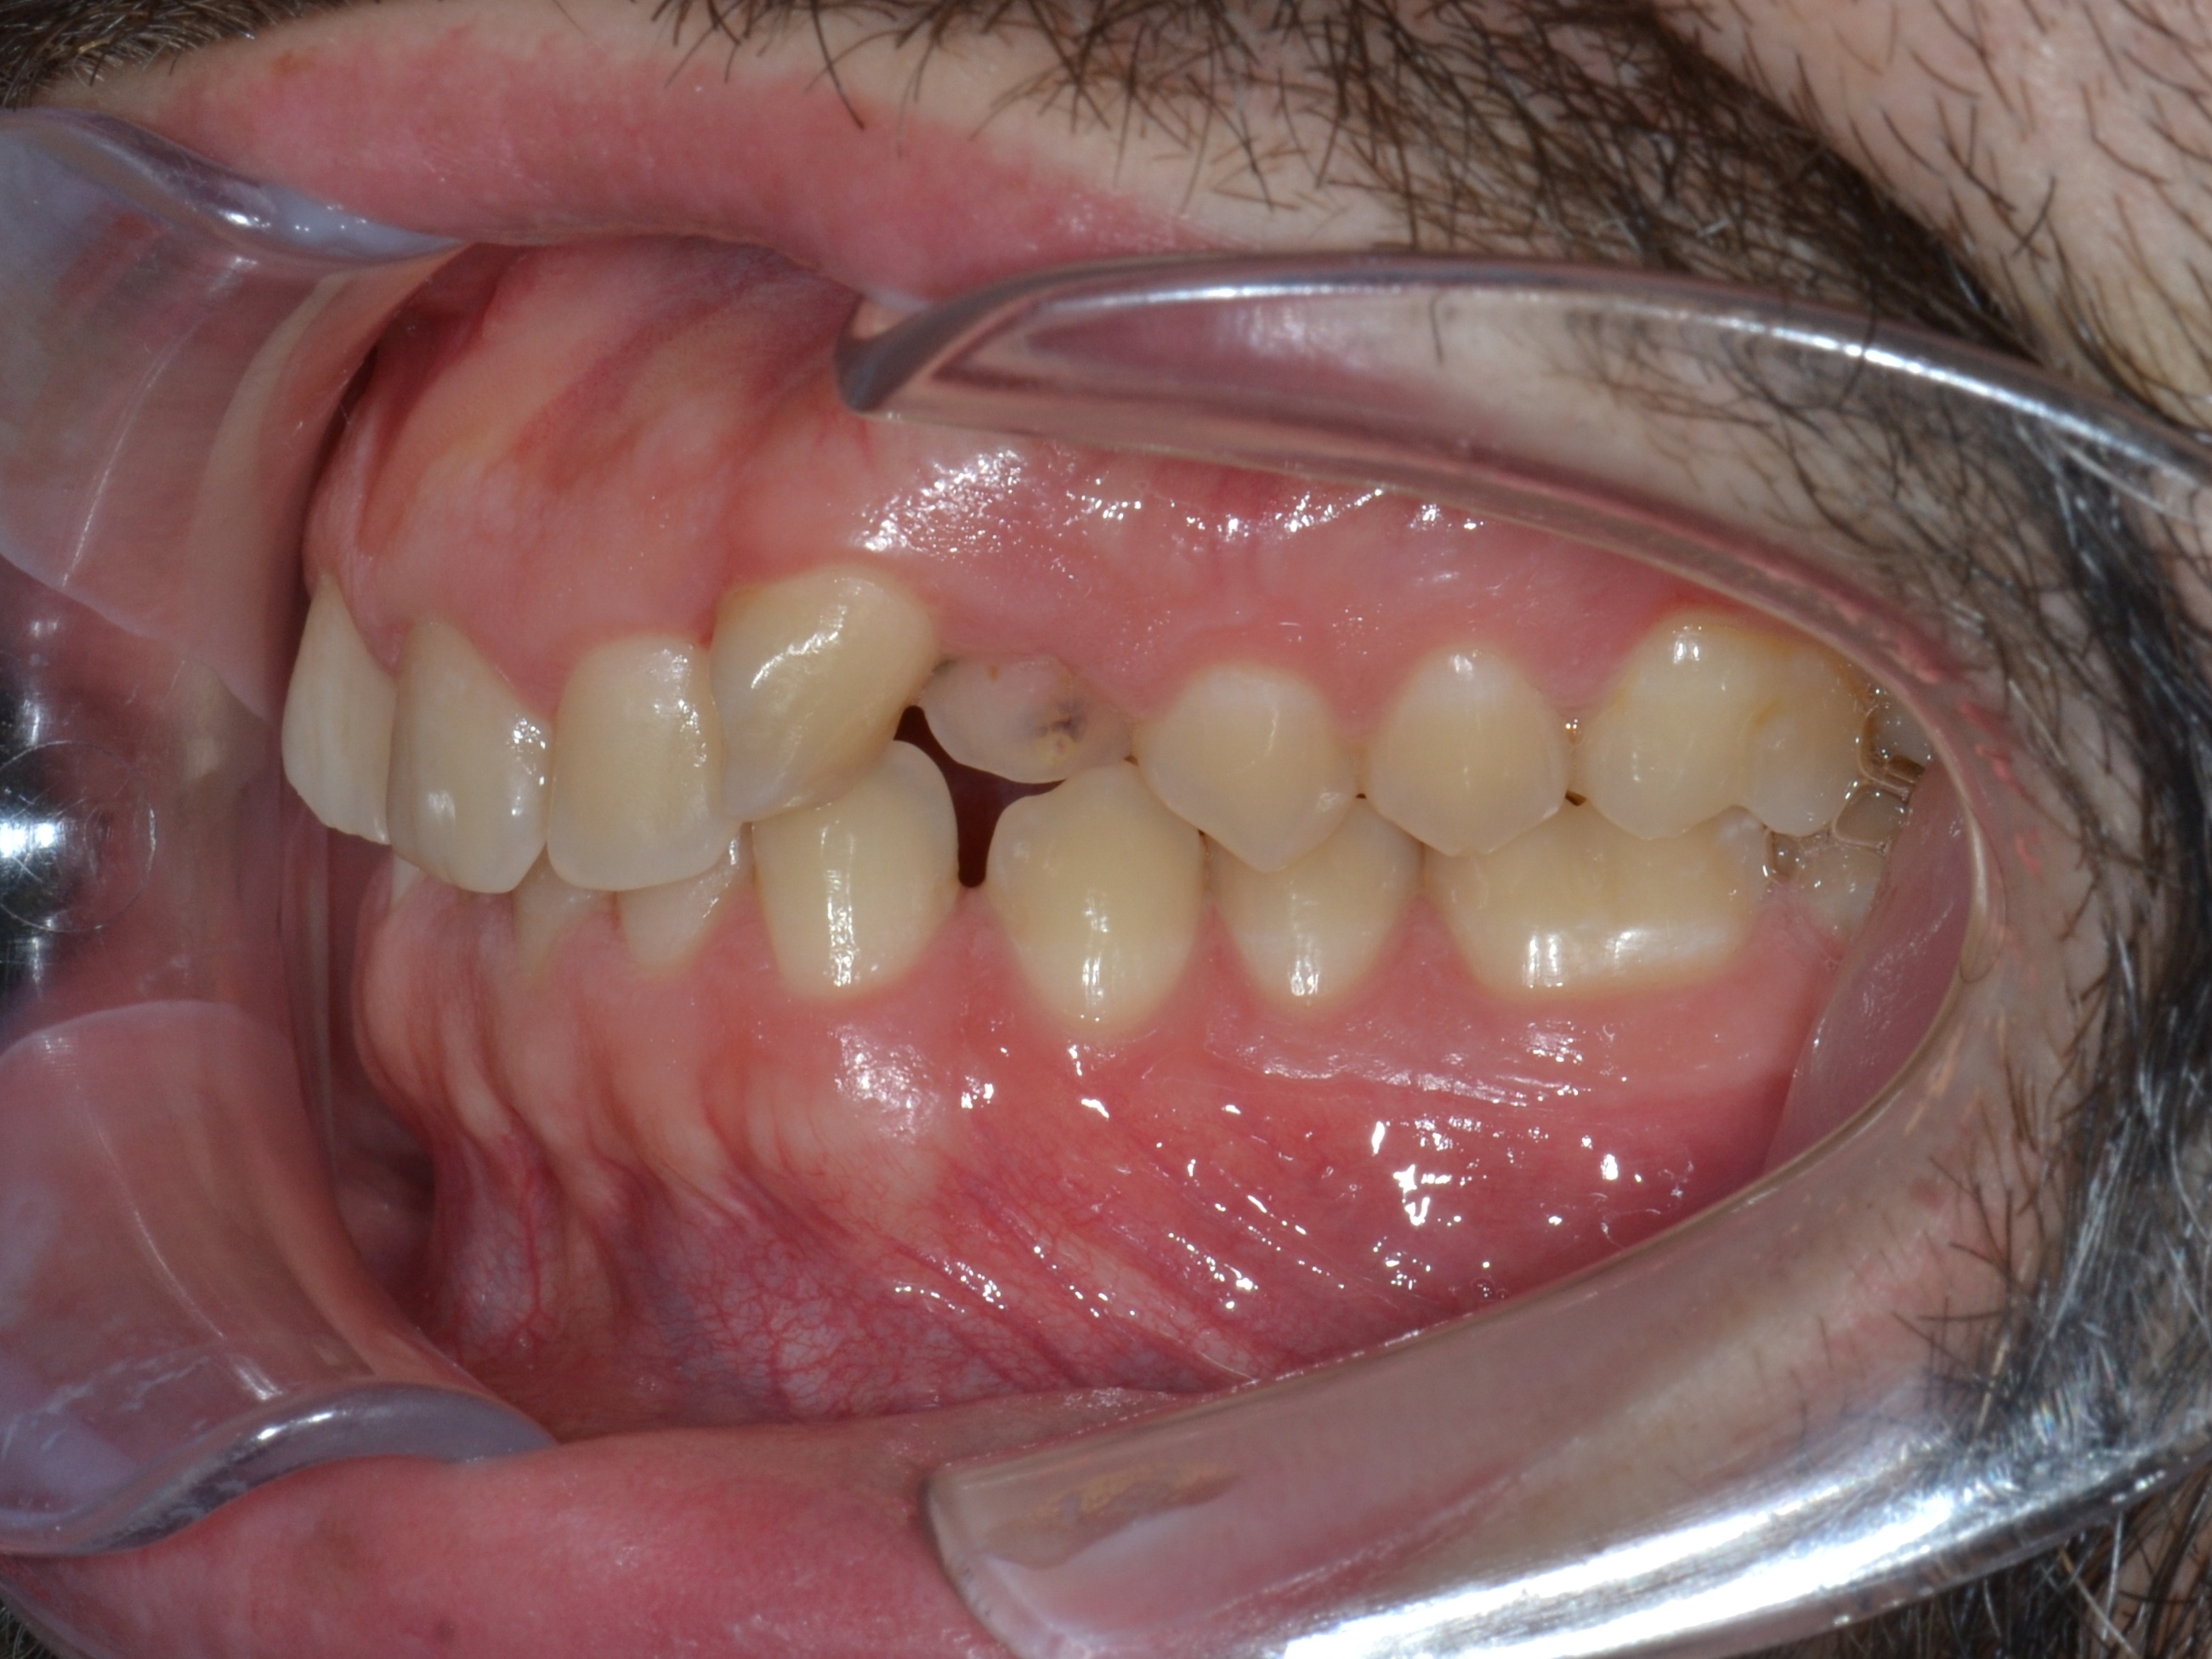

Выявленные проблемы

• Дистальная окклюзия ||(2)

• Глубокое резцовое соотношение

• Скученность фронтальных зубов

• Вестибулярное положение клыков

Брекет-система Ultra